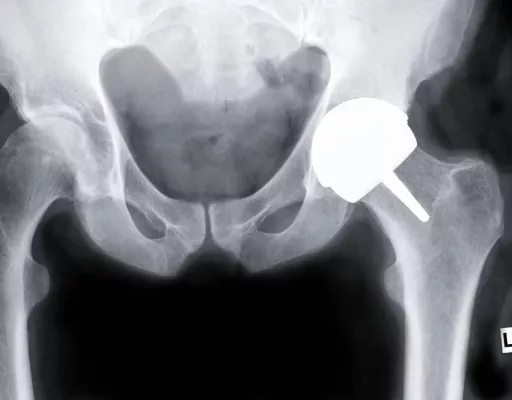

Oberflächenersatzprothese:

Alternatives Operationsverfahren für Hüftgelenksersatz.

Bei minimalem Knochenverlust wird der Hüftkopf wie ein Zahn „überkront“!

Bisher wurde bei Hüftgelenksoperationen der Hüftkopf zusammen mit dem gesamten Schenkelhals entfernt und ein ca.15 cm langer Metallstiel in den Oberschenkelknochen eingebracht. Dabei ging auch ein Großteil gesunder Knochensubstanz verloren. Beim neuen Verfahren wird nur noch die abgenutzte Oberfläche des Hüftkopfes abgefräst und mit einer Kappe überkront - ähnlich wie dies bei einem Zahn geschieht. Die zerstörte Gelenkpfanne wird mit einer dünnen Metallschale ausgekleidet.

„Der Vorteil gegenüber den herkömmlichen Prothesen ist das knochenerhaltende und schonende Verfahren. Wegen der Rekonstruktion der anatomischen Kopfgröße behält der Patient einen annähernd gleichen Bewegungsumfang wie mit einer gesunden Hüfte. Auch die Gefahr einer Gelenkluxation ist mit diesem Implantat fast ausgeschlossen.“, erklärt Dr. Christian Kothny, der diese Original McMinn OP-Methode als einziger Chirurg in München im M.O.E.C (MünchenOrthoEndoCenter) in der Schwabinger Clinic-Dr.-Decker anwendet.